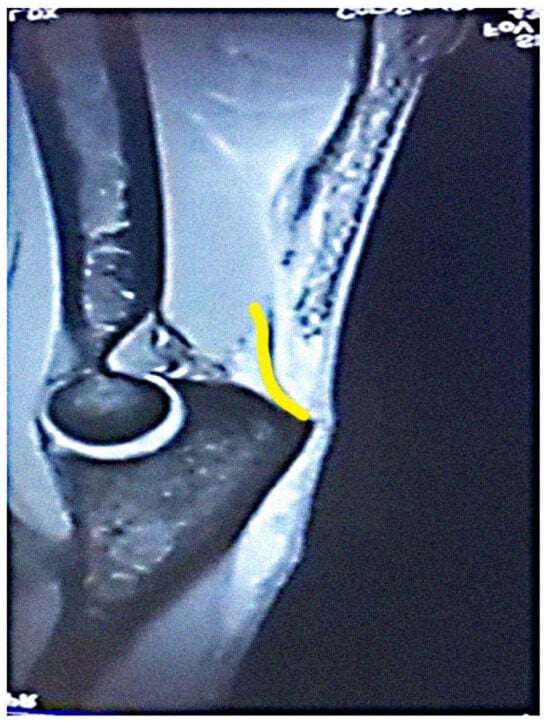

The most common tendon injuries are rotator cuff tears of the shoulder, hand flexor injuries, and achilles tendon injuries [1]. Triceps tendon rupture is the least reported among all the tendon injuries in the literature [2,3]. 65 years ago, Anzel evaluated a series of 1014 patients with tendon ruptures in various locations, and triceps tendon ruptures accounted for only 0.8% of this series [4]. Currently the prevalence is increasing, and the prevalence of triceps tendon injuries has been found to be 3.8% [5]. Theoretically, the types of tendon injuries are tendon avulsion or inside the muscle belly. In practice, a rupture almost always occurs in the area of the tendon-bone junction, and the cause is an eccentric contraction of the triceps causing a tendon deformity of more than 8% [6]. Traditionally the triceps tendon has a uniform attachment to the olecranon ulnae. This premise has caused problems in assessing the degree of damage in traumatic triceps tendon ruptures. In 2006, an anatomic study by Madsen confirmed that in most cases the medial head of the triceps has a single attachment to the olecranon ulnae [7]. This insertion is located in a deeper layer and forms a narrower part of the attachment, and very rarely is only this part damaged [8]. The long and lateral head of the triceps has a common attachment that runs more superficially, gradually extending laterally into the surrounding area towards the musculus anconeus, which helps to strengthen the bone-tendon junction. The width of the attachment correlates with the size of the olecranon and ranges from 20 to 40 mm. Paradoxically, the thickness of the tendon is not as pronounced. The attachment itself occupies a large surface area, reaching 400 mm2 in diameter and is dome-shaped [9]. These current findings are particularly important in partial tendon ruptures when a decision has to be made whether to proceed conservatively or with surgical revision. MRI is an appropriate method of choice to accurately assess the current condition. A schematic representation of the three basic types of partial DTTR rupture can be seen in Figure 1, while the normal anatomic attachment relationships of the triceps tendon in sagittal section to the olecranon ulna and a sub-complete rupture of the triceps tendon of the right hand are shown in Figure 2 and Figure 3. Furthermore, the place of attachment of the individual heads of the triceps to the olecranon ulnae is presented in Figure 4.

Figure 4. Place of attachment of the individual heads of the triceps to the olecranon ulnae (Own source).